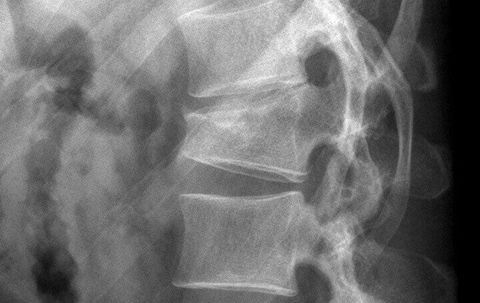

Osteoporose

Osteoporose ist die häufigste Alterserkrankung der Knochen, auch als „Knochenschwund“ bekannt. Sie ist durch eine Abnahme der Knochendichte gekennzeichnet, wodurch die Frakturanfälligkeit erhöht wird. Mit Hilfe der Knochendichtemessung (DXA-Messung) können wir Sie präventiv beraten oder eine entsprechende Therapie frühzeitig einleiten, um z.B. Brüche der Wirbelkörper bzw. des Oberschenkelhalses zu verhindern.

Häufig betroffene Körperregionen:

- Lendenwirbelsäule